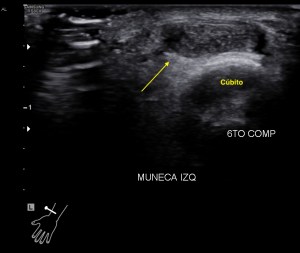

Lo que ves en estas imágenes que te voy a poner aquí son los hallazgos ecográficosque he podido visualizar hoy. Los voy a complementar con la correlación con las imágenes de TAC. En este caso específico con la eco solo se pudo corroborar los hallazgos del escáner, que a nivel anatómico arroja un mejor desarrollo de la anatomía regional implicada en el proceso.

6En el corte longitudinal de la imagen 1 ya se ve una vaso perimetrado por una imagen hiperecogénica, no compresible a la presión con la sonda convexa. En la imagen 2 con la sonda lineal se observa el enrejado habitual de los stents, que en otras ocasiones ya hemos comentado en otro post en localización distinta.